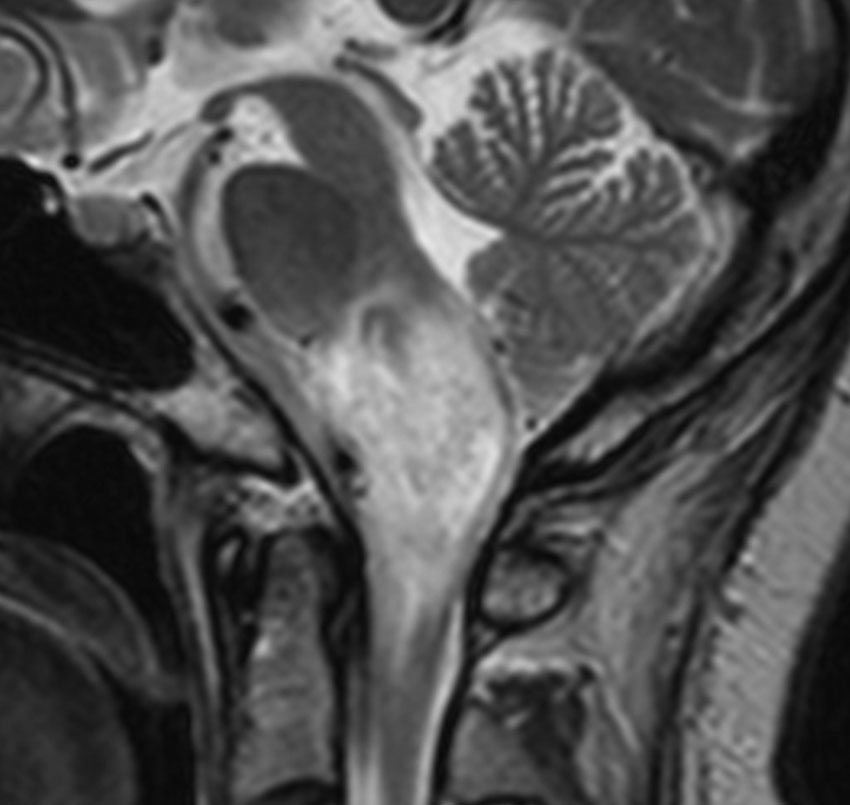

30代の患者さんです。起立性低血圧や呼吸苦,右片麻痺と多彩な脳神経症状で発症しました。

左はT2強調画像で,延髄を中心とするびまん性グリオーマの所見です。右はがドリニウム増強像で,一部が増強されて白く見えています。

50.6Gy/28fr, TMZ 24コースの治療をした4年後のMRIです。腫瘍は縮小して固まったようにみえ,症状も落ち着いて自宅で暮らせてました。

しかしこの後に,激しい腫瘍再燃があり制御できませんでした。